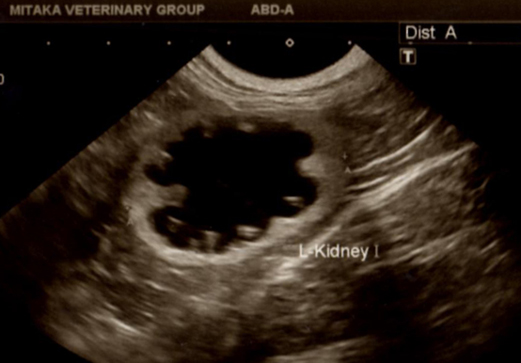

診断の方法は、腎臓に水が溜まる(腎盂に溜まる)状態すなわち水腎症があるか、尿管に水が溜まり拡張しているか、の有無が参考になります。これは通常、腹部の腎臓の超音波検査で判定できます。腎臓のX線検査でも、X線不透過性の結石の場合は、その位置、大きさと数、また腎臓の結石の有無でも判定できる場合があります。問題は二つある腎臓のどちらに尿管閉塞があるか?ということです。通常は正常より大きくなった腎臓が閉塞のある腎臓ですが、超音波検査で結石、水腎症や水尿管症、X線検査で結石、尿管の位置や変化等の所見が参考になります。不幸なことに両方の腎臓の尿管に閉塞がある場合も約20-25%存在します。しかしこの場合は、尿がまったく出ませんので、尿道の閉塞との鑑別さえできれば、比較的容易に診断できます。

↑左の腎臓の水腎症、腎臓の中が黒く(水分の貯留)見える、結石のため尿管からの逆流したため、腎臓に水が溜まる。